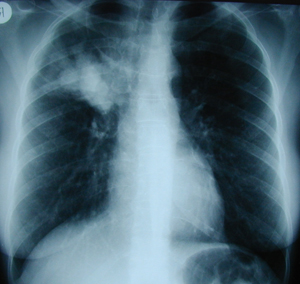

Εικόνα 4

Οπισθιοπροσθία ακτινογραφία θώρακος πολλά χρόνια μετά από δεξιά πνευμονεκτομή. Πλήρης κατάληψη του χώρου της πνευμονεκτομής από υγρό, υπερέκπτυξη του αριστερού πνεύμονος και έλξη του μεσοθωρακίου προς την χειρουργηθείσα πλευρά.